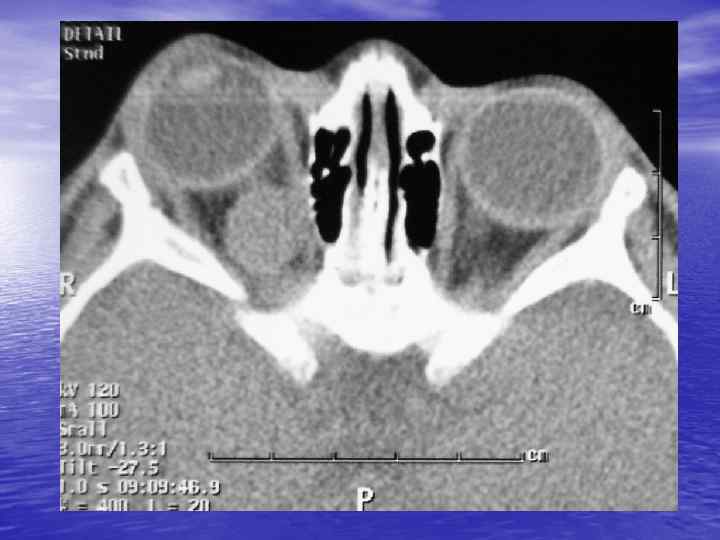

Структурный анализ Оценка основных макроскопических признаков: - положение - форма - размеры - характер контуров и структур патологически измененных участков

Структурный анализ